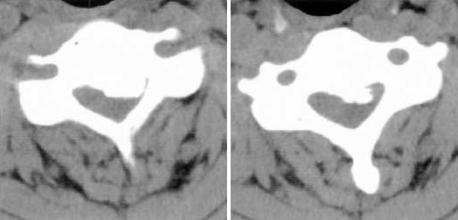

Acute neurologic deterioration is not a rare event in the surgical decompression for thoracic spinal stenosis. We report a case of transient paraparesis after decompressive laminectomy in a 50-yr-old male patient with multi-level thoracic ossification of the ligamentum flavum and cervical ossification of the posterior longitudinal ligament. Decompressive laminectomy from T9 to T11 was performed without gross neurological improvement. Two weeks after the first operation, laminoplasty from C4 to C6 and additional decompressive laminectomies of T3, T4, T6, and T8 were performed. Paraparesis developed 3 hr after the second operation, which recovered spontaneously 5 hr thereafter. CT and MRI were immediately performed, but there were no corresponding lesions. Vascular compromise of the borderlines of the arterial supply by microthrombi might be responsible for the paraparesis.

在胸椎椎管狭窄症的手术减压中,急性神经功能恶化并非罕见事件。我们报告了一例50岁男性患者,该患者患有多节段黄韧带骨化和颈椎后纵韧带骨化,在进行减压性椎板切除术后出现短暂性截瘫。对T9至T11进行了减压性椎板切除术,但神经功能未得到明显改善。首次手术后两周,进行了C4至C6的椎板成形术以及T3、T4、T6和T8的额外减压性椎板切除术。第二次手术后3小时出现截瘫,5小时后自行恢复。立即进行了CT和MRI检查,但未发现相应病变。微血栓对动脉供应边界的血管压迫可能是导致截瘫的原因。